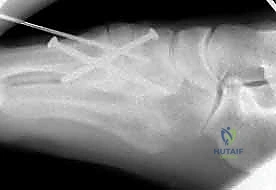

1. الرد المفتوح والتثبيت الداخلي (ORIF - Open Reduction and Internal Fixation)

هذا هو الإجراء الكلاسيكي والأكثر شيوعاً. يهدف إلى إعادة العظام إلى مكانها الطبيعي (الرد) وتثبيتها باستخدام معدات طبية (مسامير، شرائح، أو أسلاك) حتى تلتئم الأربطة والعظام.

خطوات العملية:

4. التثبيت (Fixation): يتم تثبيت العظام باستخدام مسامير معدنية خاصة (Solid or Cannulated Screws) تعبر المفاصل لتثبيتها بإحكام. في بعض الحالات، يتم استخدام شرائح معدنية صغيرة للحفاظ على الاستقرار.

5. مسمار ليزفرانك: الخطوة الأهم هي وضع "مسمار ليزفرانك" (Lisfranc Screw) الذي يمر من العظم المسماري الإنسي إلى قاعدة المشط الثاني، لتعويض وظيفة الرباط الممزق.